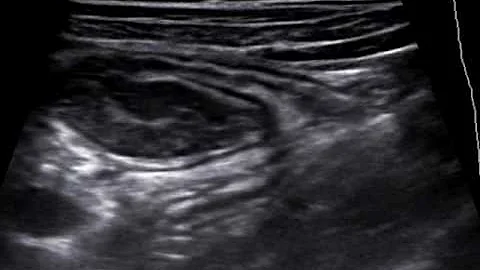

Invagination ! In Ultrasound

suitable for all #residents an medical doctor even how loves knowledge :) have a question?? comment please and ...